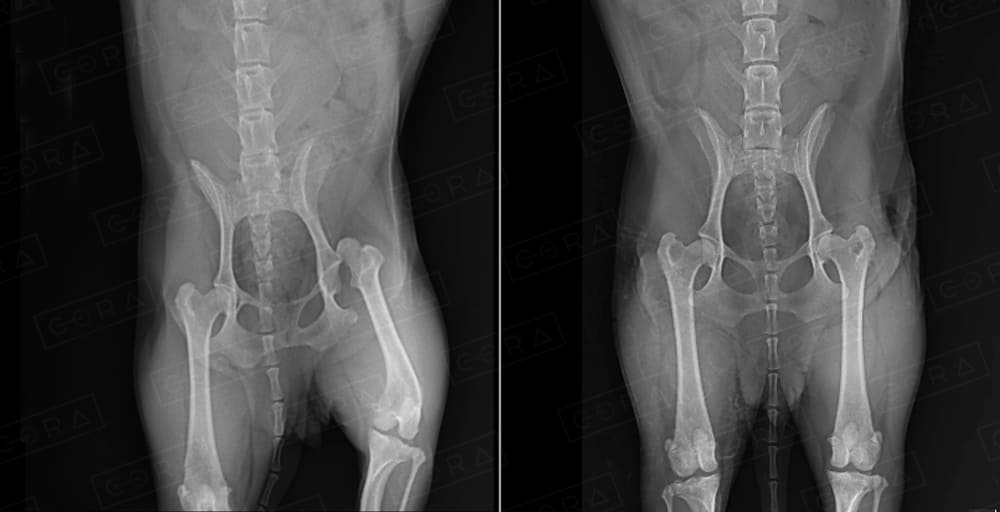

O diagnóstico é clínico e radiográfico. Algumas vezes são necessários demais exames complementares, como tomografia computadorizada.

Existem diversas técnicas de tratamento, desde as conservativas (com talas e bandagens) até as cirúrgicas, com o uso de implantes (placas, pinos, fios de aço, hastes bloqueadas, fixadores externos).